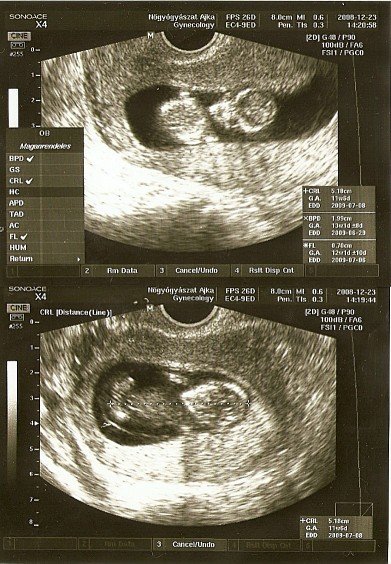

Én hétfőn voltam a 12. heti vizsgálaton. Minden rendben van a babával odabent!

Nagyon sokat mocorgott, és a külső ultrahanggal megérte az orvosom követni, hogy a kötelező méréseket el tudja rajta végezni. Végül is sikerült, 65mm volt a CRL, a nyaki redő pedig 1,1 mm, és nagy nehezen az orrcsontját is láttuk. A bal kezét folyamatosan az arca előtt tartotta, és szerintem az ujját is szopizta.

Nagyon aranyos volt, folyamatosan izgett-mozgott, pörgött odabent, most még sok helye van erre. A 9. heti vizsgálathoz hasonlóan megtartotta az 5 napos előnyét a menzeszhez való számoláshoz képest. De a vonalzót nem módosítottam. Most is kaptam képeket, de azok már élményben eltörpülnek az 5 perces dvd-hez képest.